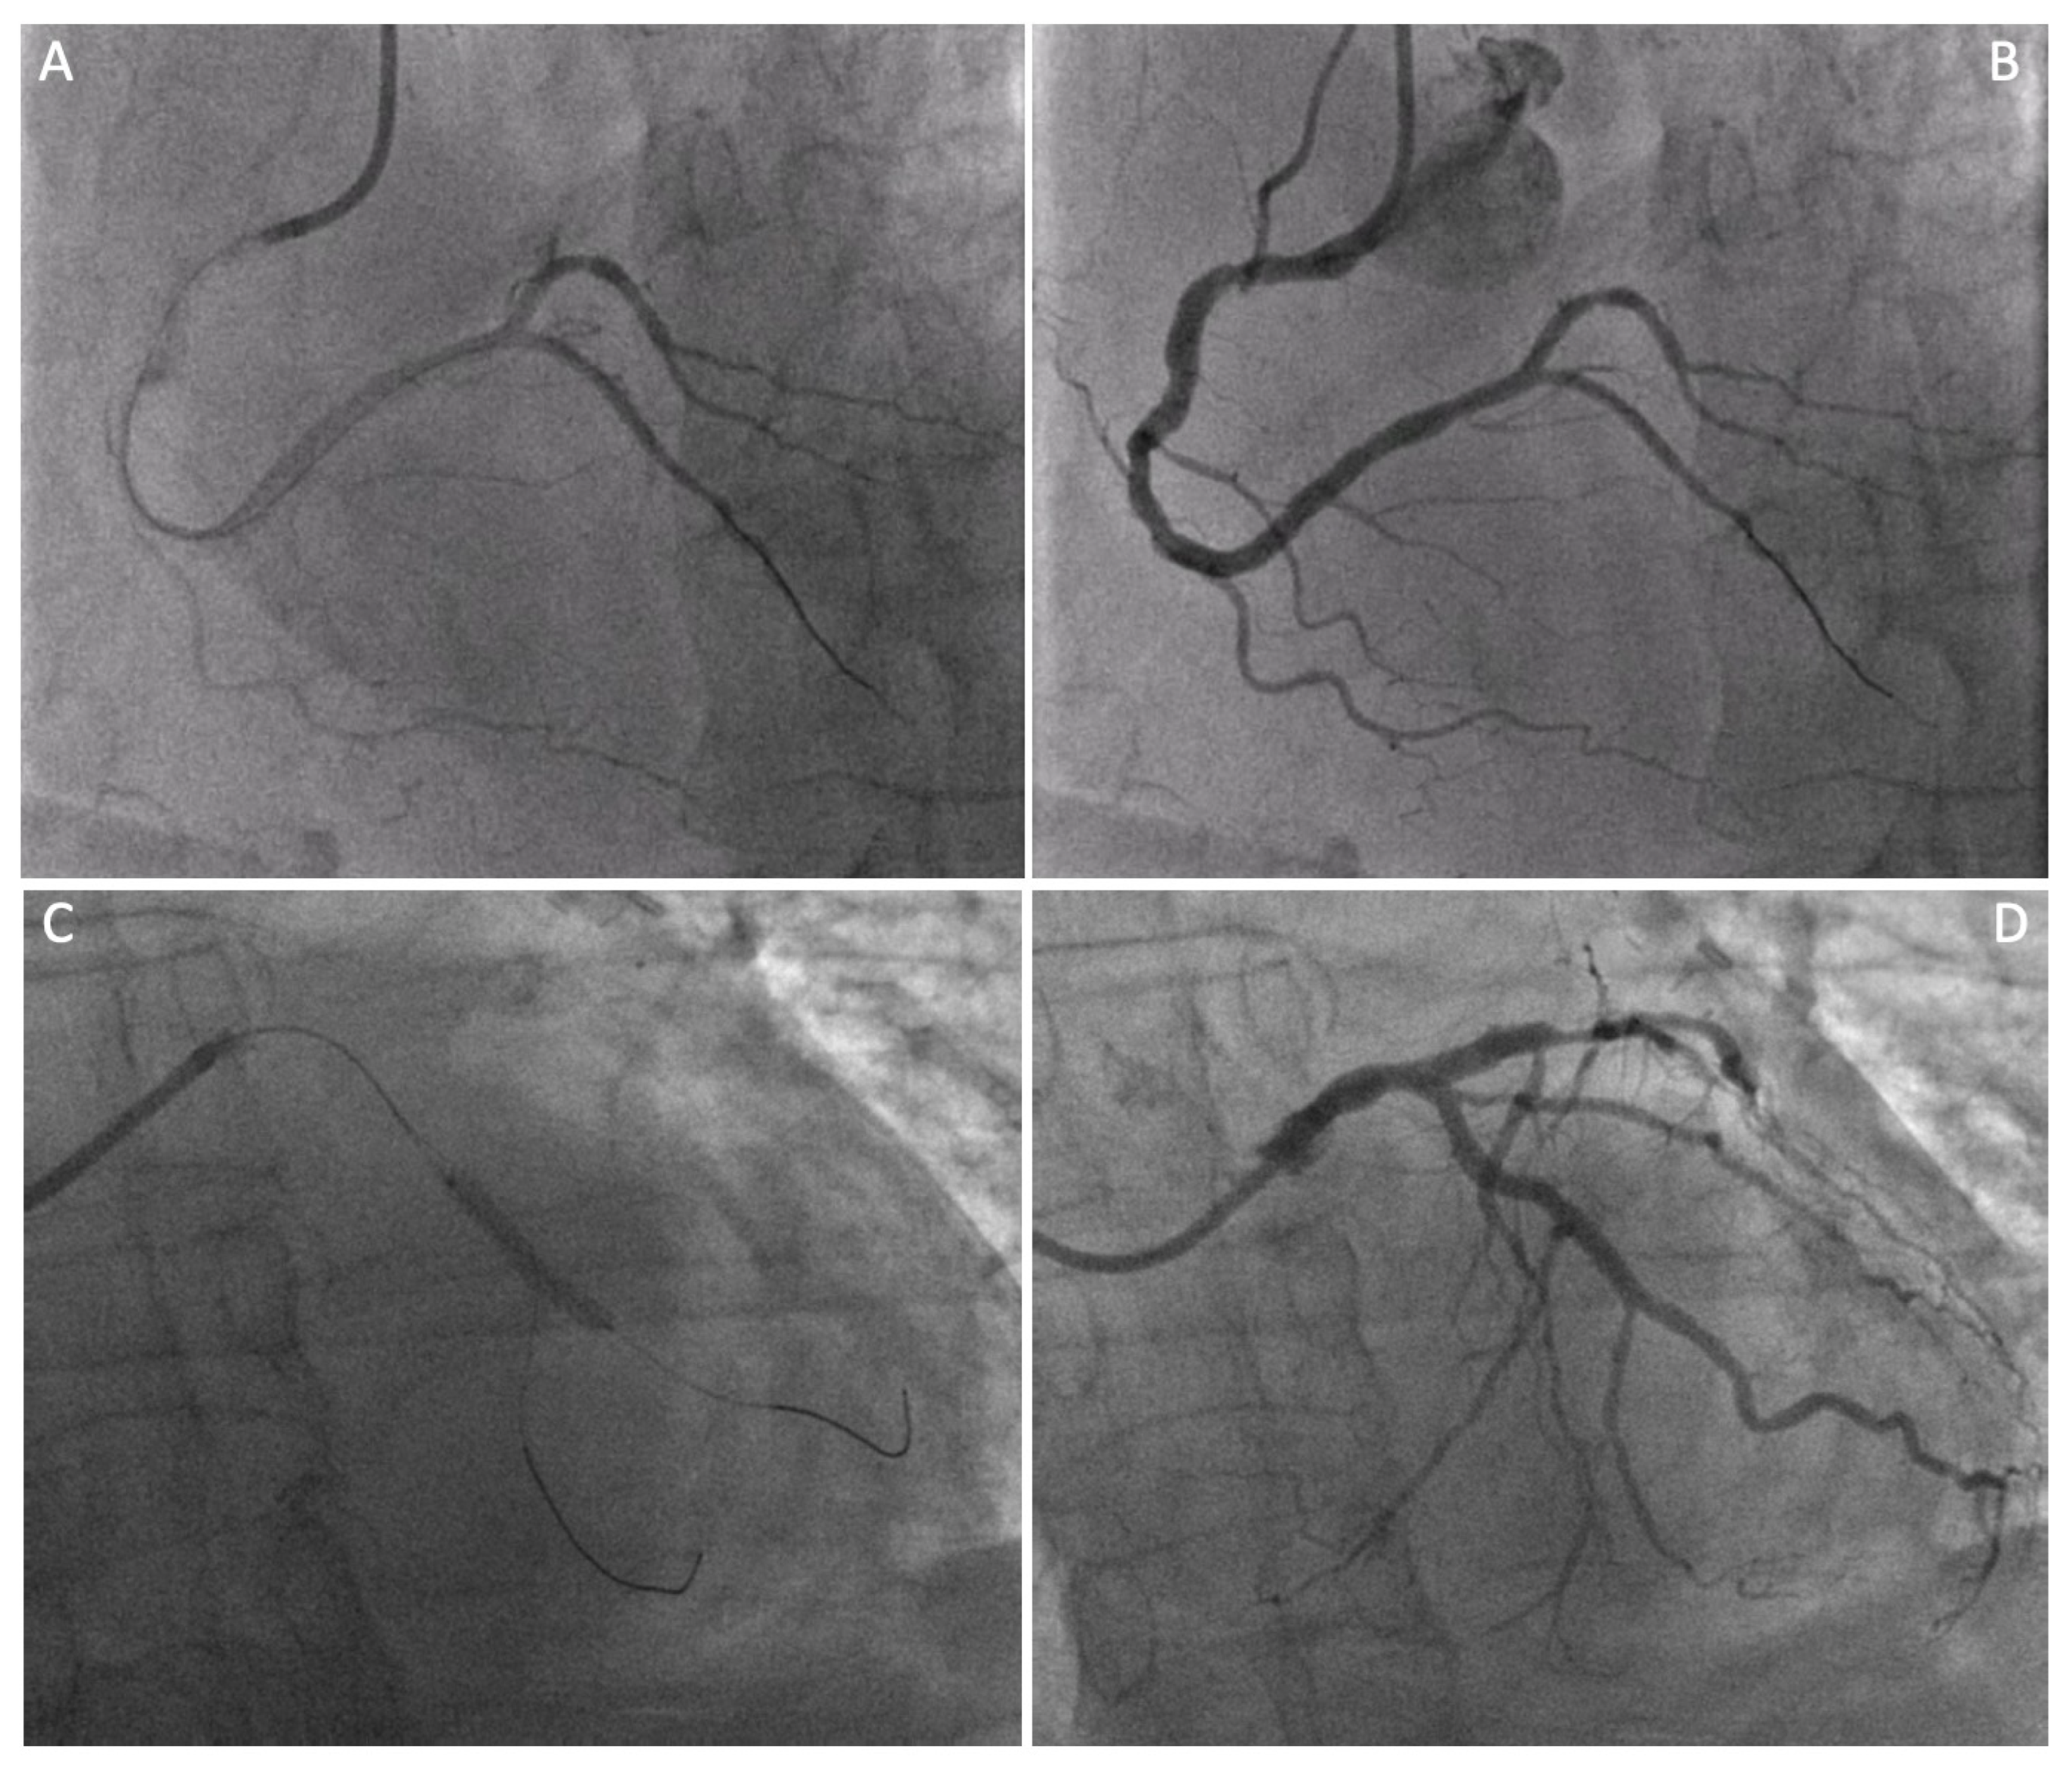

- Absence of calcification of the ascending aorta, allowing the execution of the proximal anastomosis (Figure 4A).

| LIMA angiographic patency at staged PCI (n° of pts, %) | 10 (100%) |